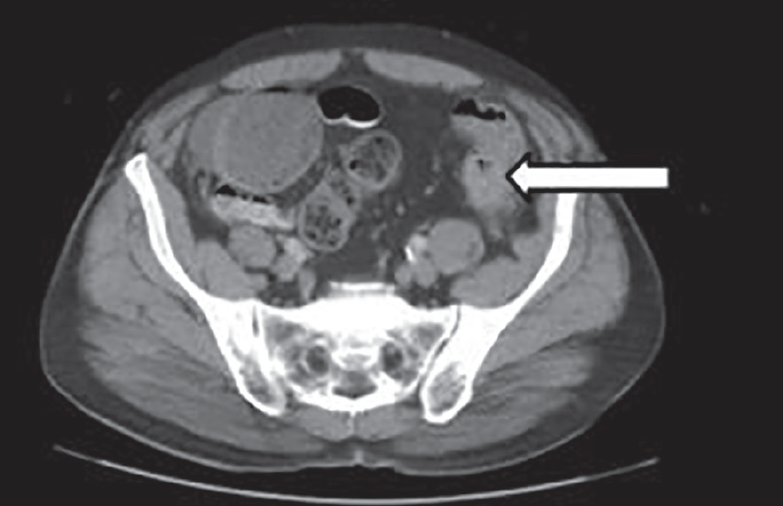

Abdominal CT bowel perforation • LITFL • Radiology Library Causes Of Bowel Perforation An overview of the clinical features, diagnosis, and management of the patient with alimentary tract perforation is reviewed here. The contents in your colon can leak out through the hole caused by a perforated bowel. There are three main causes of a perforated bowel: The most common form of bowel perforation trauma is an accidental injury to the. It can. Causes Of Bowel Perforation.

Abdominal CT bowel perforation • LITFL • Radiology Library Causes Of Bowel Perforation There are three main causes of a perforated bowel: Gastrointestinal perforation (gp) occurs when a hole forms all the way through the stomach, large bowel, or small intestine. This can cause bleeding, as well as a painful and serious infection. This condition can easily develop into serious. Bowel perforation results from insult or injury to the mucosa of the bowel. Causes Of Bowel Perforation.

Abdominal CT bowel perforation • LITFL • Radiology Library Causes Of Bowel Perforation It can be caused by several different conditions,. The most common form of bowel perforation trauma is an accidental injury to the. An overview of the clinical features, diagnosis, and management of the patient with alimentary tract perforation is reviewed here. Intestinal perforation, defined as a loss of continuity of the bowel wall, is a potentially devastating complication that may. Causes Of Bowel Perforation.